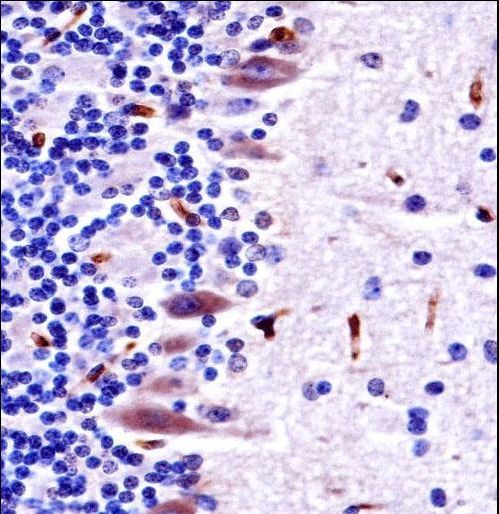

- Experimental details

- Mouse Mlk4 Antibody immunohistochemistry of formalin-fixed and paraffin-embedded mouse cerebellum tissue followed by peroxidase-conjugated secondary antibody and DAB staining.